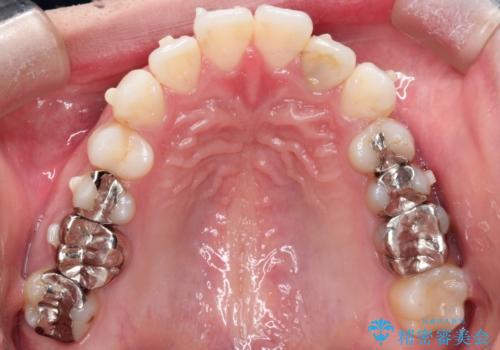

インビザラインで目立たない矯正 ガタガタの歯並びをきれいな歯並びへ

歯と歯のあいだをわずかに削りスペースを作り、ガタガタを改善する計画としました。

装着時間をしっかり守っていただけたのでスムーズに治療をすすめることができました。